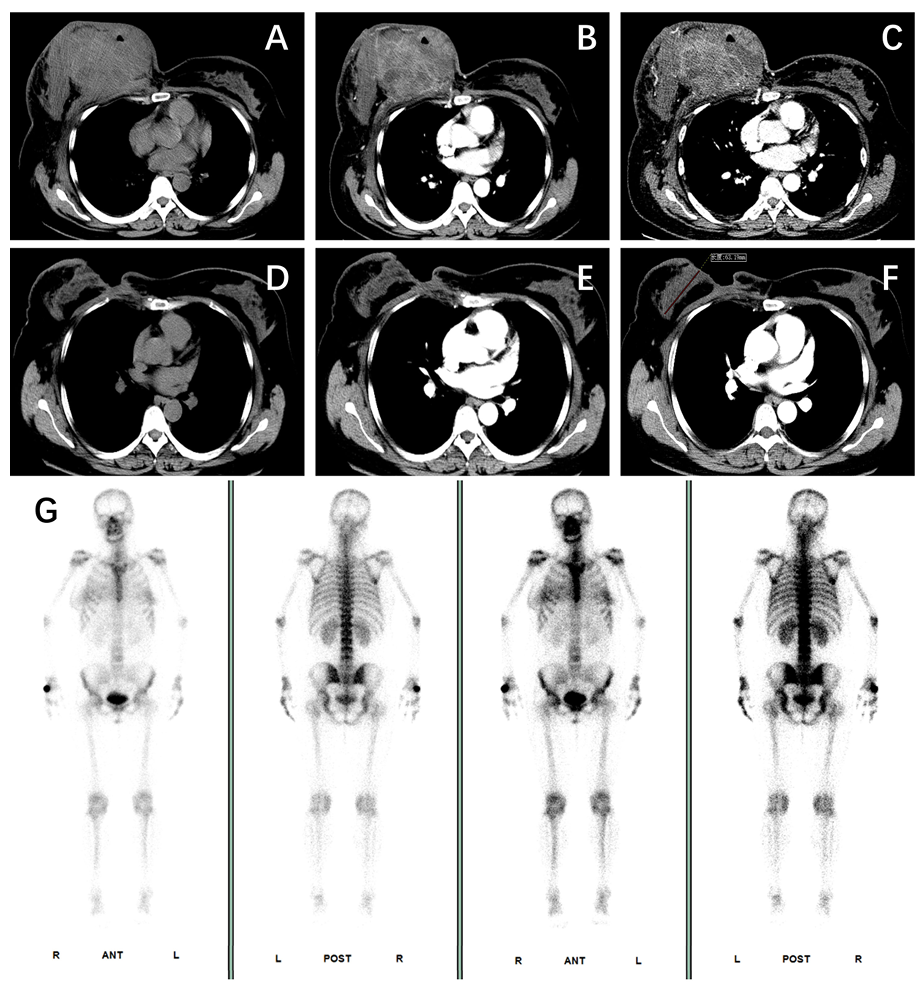

患者完成4周期化疗及3周期免疫治疗后,临床应答显著:右侧乳房肿块明显缩小,表面皮肤溃疡完全愈合。复查胸部增强CT证实乳腺肿瘤及腋窝淋巴结显著退缩,全身骨扫描未见远处转移征象。

17.png图2 患者增强CT图像及全身骨扫描。A-C:基线;D-F:NAT后。

随后患者接受根治性手术治疗(右侧扩大根治术乳房切除术+右侧扩大根治术乳房切除术+双侧游离腹壁下深动脉穿支皮瓣乳房重建)。术中快速病理检查示右侧腋窝前哨淋巴结反应性增生(14枚均阴性),冰冻切片未查见癌细胞。右侧乳房切除标本及43枚腋窝淋巴结最终病理检查结果显示,患者达到pCR。患者术后恢复良好,术后2周重启辅助化学免疫治疗,顺利出院。